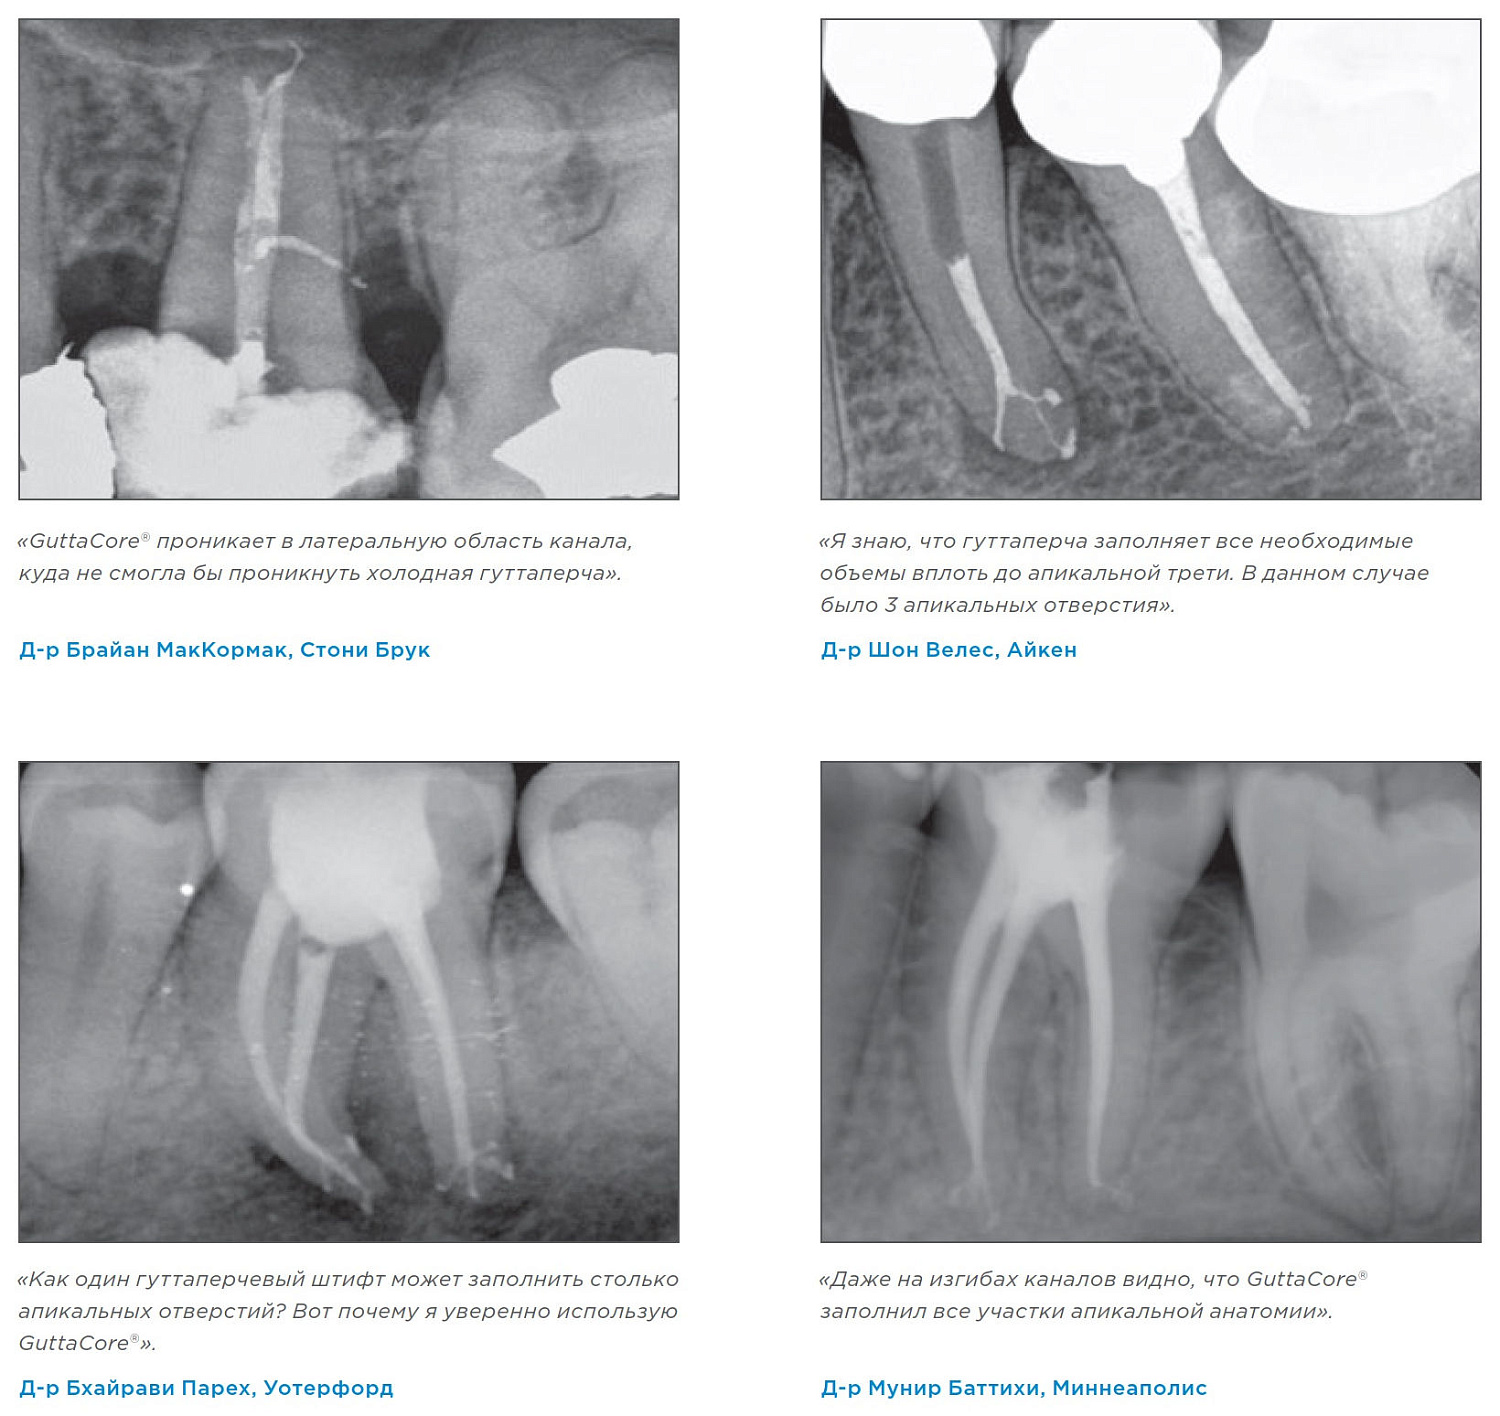

Способность GuttaCore полностью заполнять объем корневого канала в соответствии с его анатомией позволяет уверенно проводить обтурацию даже в сложных клинических случаях.

Многочисленные клинические исследования показывают эффективность полного заполнения всей системы корневого канала с помощью GuttaCore в сравнении с другими техниками обтурации. GuttaCore обеспечивает самое высокое содержание гуттаперчи и минимальное количество корональных и апикальных пустот, в отличие от техники латеральной компакции.